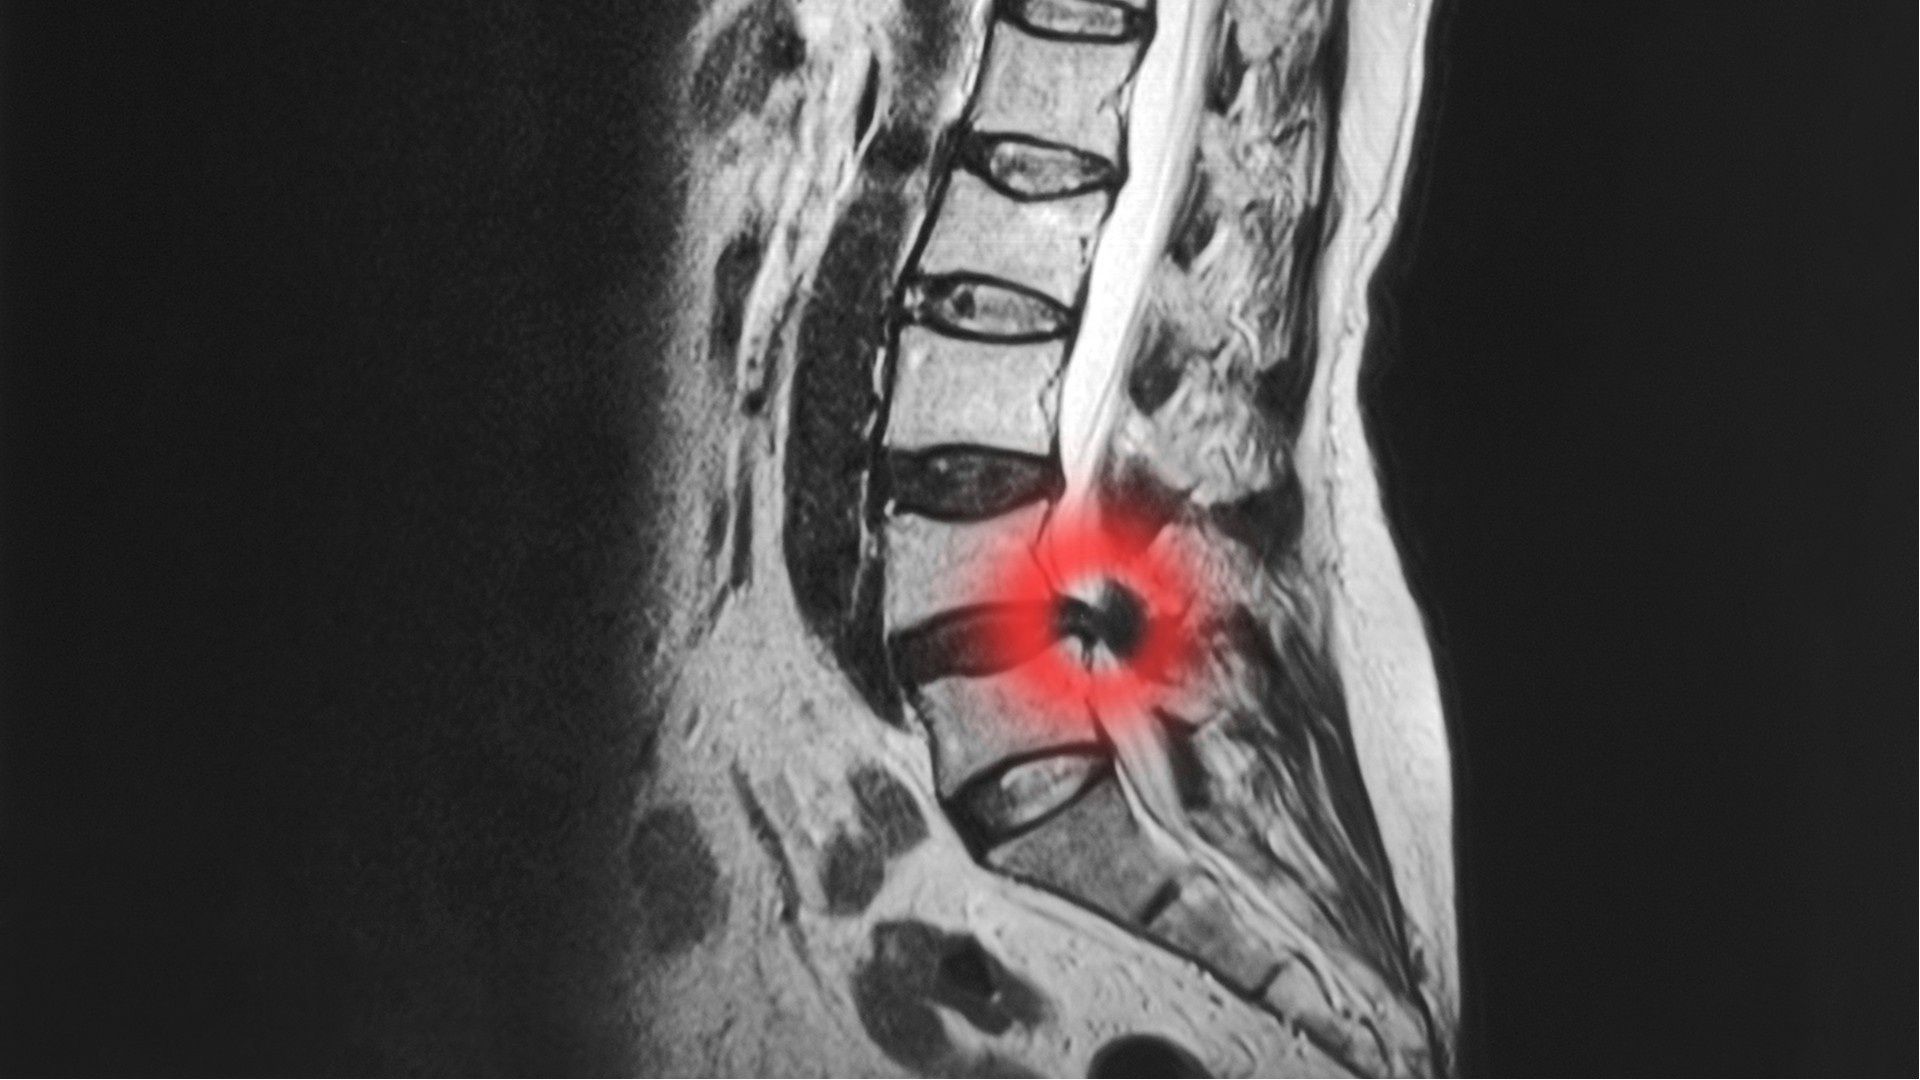

Herniated or Bulging Discs

Damage to the disc tissue between each vertebrae can cause it to change shape. This can be a mild bulging or a herniation of disc tissue, causing it to press on the spinal canal and/or nerves, causing Stenosis.